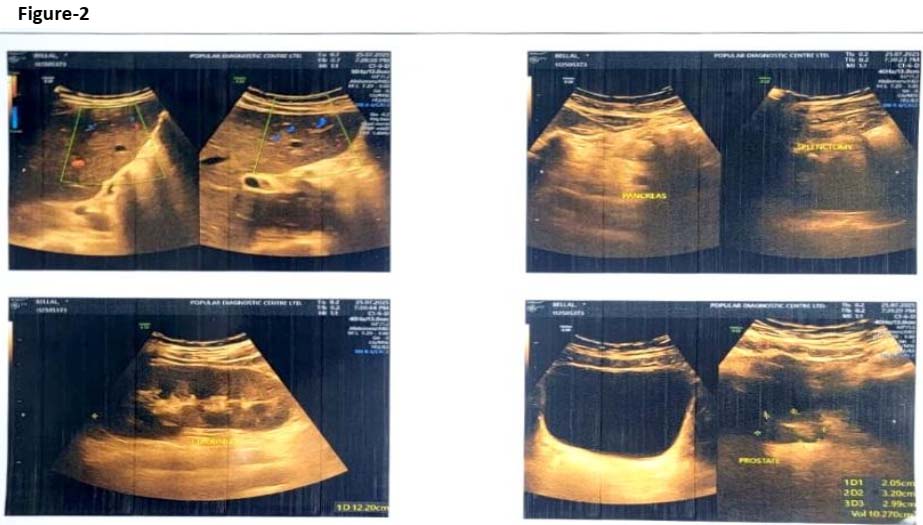

A 24-year-old male student hailing from Barguna, a coastal area of Barishal district of Bangladesh, with a known history of Hb-E β-thalassemia major was admitted to a tertiary care hospital in the capital Dhaka with the chief complaints of fever for 20 days (maximum temperature recorded 104°C), dyspnoea for 5 days along with right-sided neck swelling for 3 days. The patient was diagnosed as a case of Hb E β-thalassemia major at 3 years of age based on complete blood count, Hb-electrophoresis and iron profile. He had splenectomy in 2008, following which regular blood transfusions were required every 3-4 weeks. On general examination, temperature was 103.8°C, blood pressure was 90/60 mmHg, SpO₂ was found 92% (room air). A swelling was present on the right side of the neck along with pallor and hepatomegaly. Respiratory findings revealed bilateral crepitations. The patient’s blood analysis demonstrated hemoglobin: 6.8 g/dL, total WBC: 23,170/µL (neutrophil count: 16,682/µL), platelets: 120,000/µL. Serum bilirubin was 4.6 mg/dL, while SGPT was found 130 U/L. Iron profile revealed total iron: 25.84 µg/dL, TIBC: 93 µg/dL and serum ferritin: 12,440.45 ng/mL (normal: 20–300 ng/mL in adult males). Ultrasonography of whole abdomen showed multiple tiny cystic lesions in both lobes of the liver suggestive of micro-abscesses, along with bilateral pleural effusion. Chest X-ray was advised but could not be done because of deteriorated condition of the patient. Blood culture revealed growth of B. pseudomallei, sensitive to ceftazidime, meropenem, co-amoxiclav, co-trimoxazole, and doxycycline; resistant to aminoglycosides and colistin. Therefore, the case was finally diagnosed as septicemic melioidosis in a β-thalassemic major patient. The patient was started on intravenous meropenem 6 days following the onset of symptoms (2 g every 8 hours) along with supportive transfusions and oxygen supplementation. Despite initial stabilization, his fever persisted, and respiratory status worsened. After 11 days of hospitalization, and 7 days of antibiotic administration, he succumbed to septicemia and multi-organ failure.

Figure-2: Ultrasonography of abdomen showing presence of multiple micro-abscesses in the liver

Our patient presented with disseminated melioidosis, evident by the presence of hepatic micro-abscesses, neck abscess, pleural effusion, and sepsis. Although appropriate antibiotics were initiated within first day of diagnosis his severe iron overload and compromised immunity likely contributed to poor treatment outcome and death.